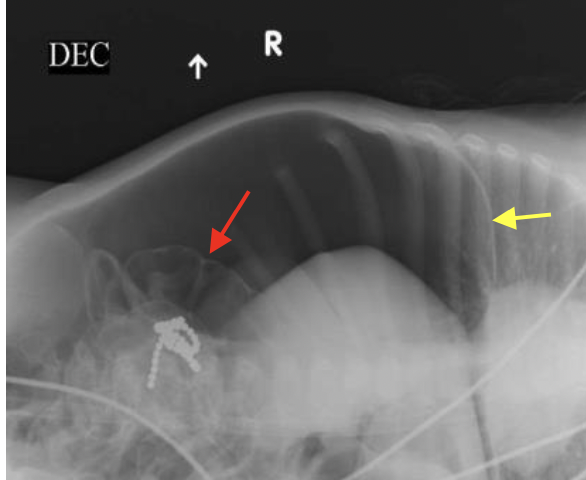

משמאל- ניתן לראות פלס אוויר- נוזל בריבה. כאשר לולאות המעי הדק רחבות מעל ל3 מ״מ זה מעיד על חסימה.

מימין- הצילום נעשה בשכיבה (שייך לאותו חולה), רואים את האוויר, אי אפשר לראות פלסים כי זה בשכיבה.

מה יש בחיצים?

צהוב- פס דקיק של הסרעפת

אדום- מעי, ניתן לראות את הדפנות בגלל שיש נוכחות חופשית של אוויר בחלל הבטן. למה יש נוכחות חופשית של חלל הבטן? כי ההורים הביאו יותר מדי ילדים וילד בלע שרשרת מגנטים שעשתה לו פרפורציה.